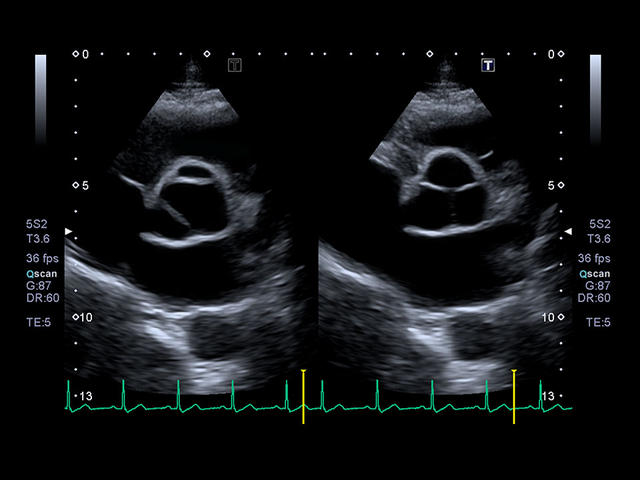

- Кардиология

- Превосходное качество изображений и максимальная детализация. Четкое прорисовывание границ и повышенная однородность изображения позволяют без сомнений устанавливать точный диагноз.

- Секторный фазированный взрослый

- Секторный фазированный педиатрический